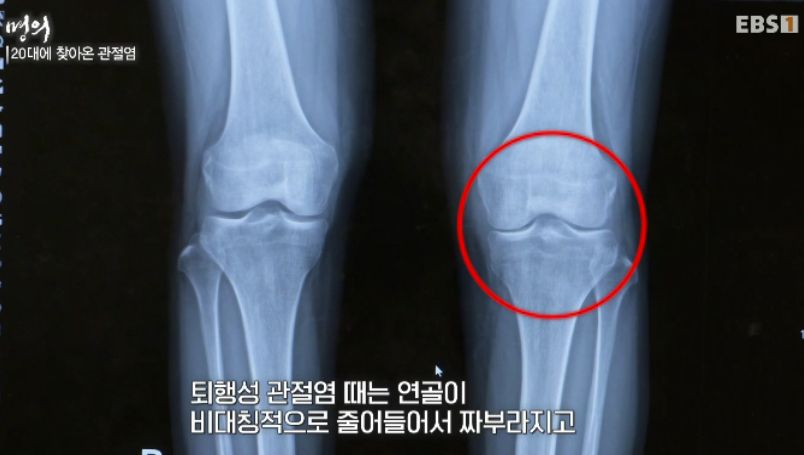

류마티스 VS 퇴행성 관절염

류마티스로 약해진 관절은 퇴행성관절염을 악화시킨다.

그래서 노인은 더 조심해야 하고 노인이 아닌 사람도 퇴행성관절염까지 대비해야 한다.

손가락끝에 아픈 것, 양 무릎 안쪽.. 노인성, 퇴행성 관절염

류마티스는 손가락 중간마디마디, 퇴행성은 손가락 끝마디,

류마티스환자는 뼈가 녹으니 그걸로 운동하면 불균형한 힘이 주어지고 그럼 퇴행성관절염이 오고 둘이 서로 악화시킨다.